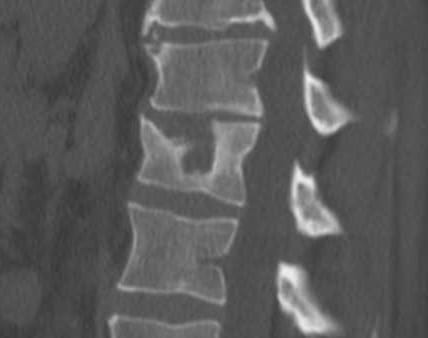

suite a un petit dysfonctionnement de L1 j'ai due me faire faire un corset, après avoir demander 3 fois le prix de la prestation sans réponse,seulement "c'est pris en charge à 100%" j'ai finalement appris que la sécu remboursait à l'orthoprothésiste, mon morceau de plastique porté 3 mois 980€; mon prothésiste en pleure encore